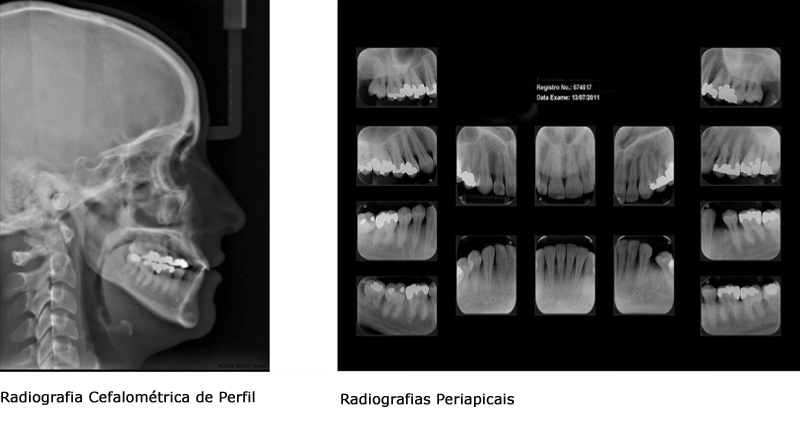

Para complementação das informações clínicas obtidas na primeira consulta, haverá necessidade de exames complementares (documentação ortodôntica) a serem realizados em centros de Imaginologia. Somente desse modo pode-se chegar a um correto diagnóstico.

A documentação ortodôntica, normalmente, inclui Radiografias dos Dentes e da Face, Fotografias e Modelos de Gesso das Arcadas Dentárias. Em situações específicas, são solicitados outros exames, como tomografias e cintilografias.